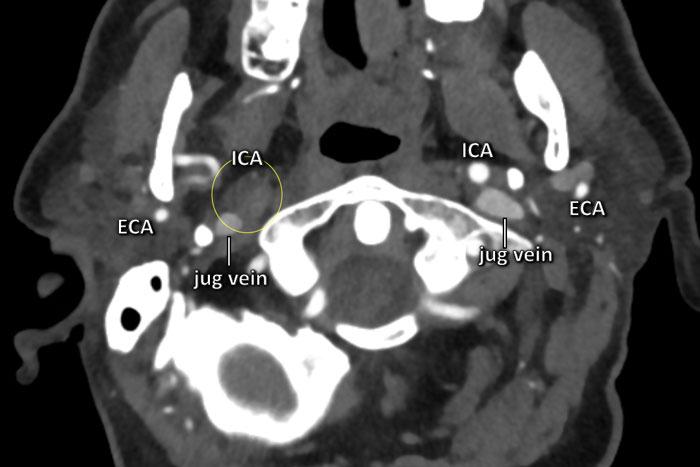

Quan sát phía dưới nền sọ

Khi nghi ngờ khả năng bóc tách mạch máu, điều quan trọng là phải khảo sát các lớp cắt ngang ngay phía dưới nền sọ như trong trường hợp này.

Ở bên trái, ICA và ECA có hình ảnh bình thường (cấu trúc tăng tỷ trọng nằm giữa hai mạch là mỏm trâm).

Ở bên phải, chúng ta thấy ECA bình thường và phía trong tĩnh mạch cảnh là ICA bị giãn (vòng tròn).

Lòng mạch không ngấm thuốc cản quang.

Sự kết hợp giữa hình ảnh tắc nghẽn trong một ICA bị giãn và phình to cho thấy chúng ta đang đối mặt với một trường hợp bóc tách mạch máu.